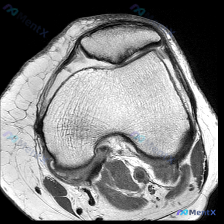

看到大家在讨论这张膝关节MRI,有人提到观察到软骨异常,我整理了完整的影像资料和分析思路,分享出来一起交流。 一、影像基本信息 这是一张膝关节MRI T1加权轴位图像,我们先梳理清楚影像上能看到的客观信息: 1. 骨骼结构:清晰显示前方三角形的髌骨和后方的股骨远端,骨髓信号均匀,和皮下脂肪信号相似,...